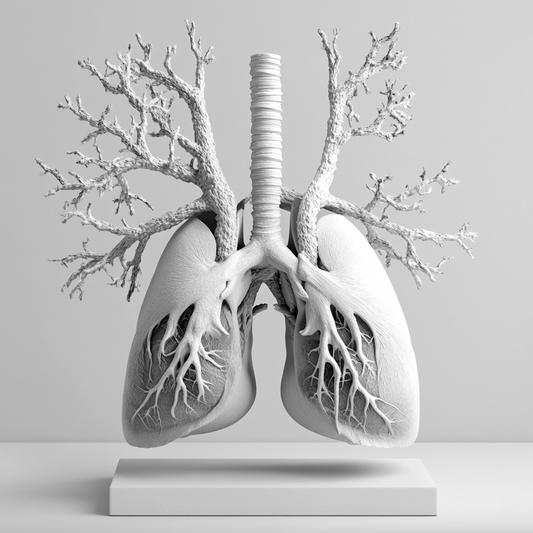

La scienza della respirazione nasale La respirazione attraverso il naso stimola la produzione di ossido nitrico (NO) nei seni paranasali. L'ossido nitrico è fondamentale per il processo di vasodilatazione, che...

La scienza della respirazione nasale La respirazione attraverso il naso stimola la produzione di ossido nitrico (NO) nei seni paranasali. L'ossido nitrico è fondamentale per il processo di vasodilatazione, che...